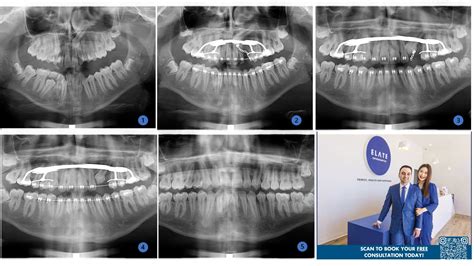

Panoramic Xray Teeth

When you visit a dentist for a comprehensive oral health assessment, you might be asked to undergo a specific type of imaging known as a panoramic Xray teeth scan. Unlike standard bitewing X-rays that focus on a few teeth at a time, this diagnostic tool captures a wide-angle view of your entire mouth, including the upper and lower jaws, the temporomandibular joints (TMJ), and the surrounding bone structures. Understanding what this procedure entails can help alleviate any anxiety you might feel before your dental appointment, as it is a safe, painless, and highly efficient way for your dentist to gain a complete picture of your oral health.

The primary advantage of a panoramic X-ray is the sheer volume of information it provides in a single image. While localized dental X-rays are excellent for detecting small cavities between teeth, they often miss larger issues hiding deep within the jaw or under the gumline. A panoramic Xray teeth image serves as a baseline for your dental history and is often the first step in creating a long-term treatment plan.

Once the image is captured, it is processed digitally and appears almost instantly on the dentist's monitor. The panoramic Xray teeth view allows your dentist to zoom in and out, highlighting specific areas of interest. You might see lines or shadows that seem confusing, but your dentist will walk you through the image, pointing out the health of your bone structure and the orientation of your tooth roots. This visual aid is an excellent educational tool, as it allows you to see exactly what the dentist sees, making it easier to understand the necessity of recommended treatments.

For example, if you have wisdom teeth, the dentist will point out their proximity to the inferior alveolar nerve—a crucial piece of information for a safe extraction. If you are experiencing jaw popping or clicking, the dentist will show you the TMJ condyles to ensure they are moving smoothly within the joint socket.